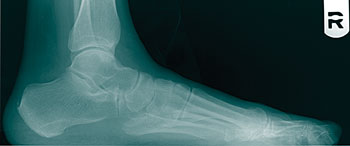

The revision bunionectomies that we have seen and performed address the undercorrection of a wide intermetatarsal (IM) angle, correction of hallux abductus and repairing a dorsiflexed capital fragment.

Nonunion of the Lapidus arthrodesis is popular to talk about but the main complication we have seen is dorsiflexion of the first ray. Other complications may include an undercorrected intermetatarsal (IM) angle and shortening of the first ray. In regard to the Lapidus procedure, while one is placing the temporary fixation, be sure to plantarflex and abduct (with laterally directed pressure) the first metatarsal.

As surgeons become comfortable with bunion surgery, we often begin to take shortcuts. For example, some may not use intraoperative fluoroscopy. It is an easy adjunctive part of a bunionectomy that only takes a couple of minutes. It can show you things you cannot always adequately visualize.These things include the position of the sesamoids, any shortening of the first metatarsal, and both the length and position of the screws.